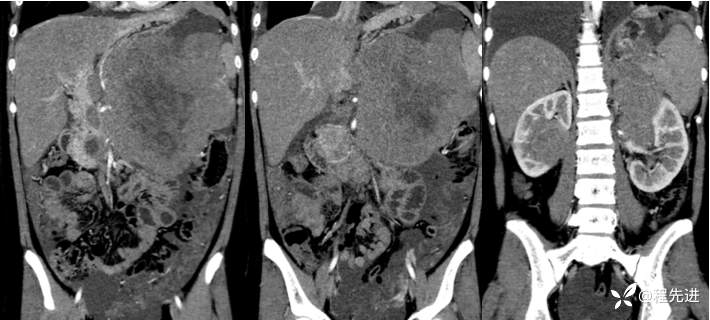

冠状位: